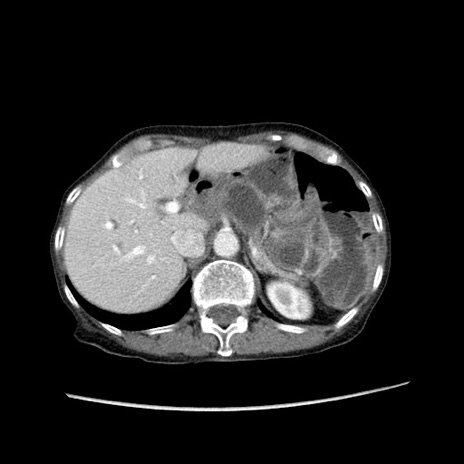

症例25(横断像)

【症例】80歳代女性

【主訴】胸のつかえ感

【現病歴】約9時間前に食後から胸のつかえた感じあり、嘔吐あり、来院。

【既往歴】胃癌(全摘)、胆摘、虫垂炎

【身体所見】心窩部に圧痛あり、反跳痛なし。

【データ】WBC 5700、CRP 0.05